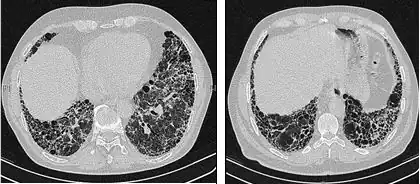

Röntgenübersichten des Thorax sind sehr nützlich bei der Verlaufsbeobachtung von IPF-Patienten. Das konventionelle Übersichtsbild führt leider zu keiner endgültigen Diagnose, kann aber ein verringertes Lungenvolumen anzeigen, typischerweise mit markanten retikulären interstitiellen Zeichnungsvermehrungen nahe der Lungenbasis.[1]

Die radiologische Untersuchung mittels HRCT ist ein grundlegendes Element der IPF-Diagnose. Ein HRCT wird mit einem konventionellen Computertomographen ohne Injektion eines Kontrastmittels durchgeführt. Die Schnittbilder zur Auswertung sind sehr dünn (1–2 mm).

Ein typisches Thorax-HRCT bei IPF weist fibrotische Veränderungen beider Lungenflügel auf, vor allem im Bereich der Basis und der Peripherie. Gemäß der gemeinsamen ATS/ERS/JRS/ALAT-Richtlinien von 2011 ist das HRCT ein maßgeblicher Bestandteil im diagnostischen Prozess der IPF, da es eine UIP bei Vorliegen folgender Merkmale identifizieren kann:[1]

- Retikuläre Verschattungen, die oft mit Traktionsbronchiektasie einhergehen

- Honigwabenmuster, gekennzeichnet durch Ansammlungen zystischer Lufträume, die meistens einen vergleichbaren Durchmesser haben (3–10 mm), gelegentlich aber auch größer sind. Sie liegen für gewöhnlich subpleural und sind durch klar abgegrenzte Wände und das Auftreten in mindestens zwei Reihen gekennzeichnet. Eine Reihe von Zysten reicht nicht aus, um als Honigwabenmuster bezeichnet zu werden.

- Milchglasverschattungen sind häufig, doch weniger ausgedehnt als die Netzstruktur.

- Die Verteilung ist typischerweise basal und peripher, jedoch häufig auch fleckförmig.